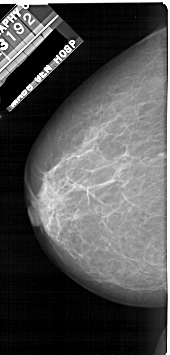

A_1922_1.RIGHT_MLO

RIGHT_MLO LINES 5101 PIXELS_PER_LINE 2671 BITS_PER_PIXEL 12 RESOLUTION 43.5 OVERLAY